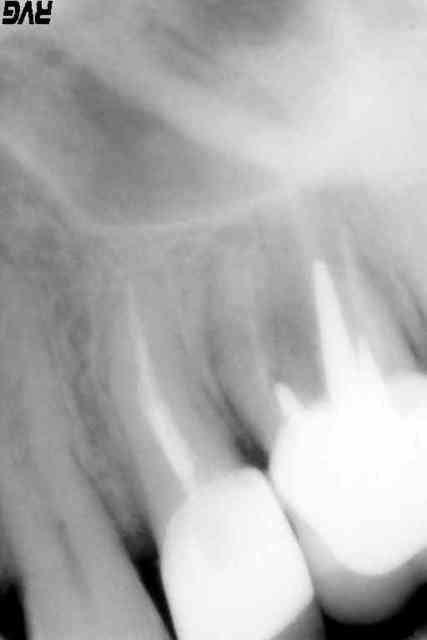

27 absente,

26 : rte faite, mais racines vestibulaires à extraire (multiples instruments cassés, et noyés dans une ancienne gutta)

j'aimerai savoir si une "prémolarisation " est possible sur cette 26 ( à savoir garder la racine palatine afin d'y loger un joli petit inlay core)